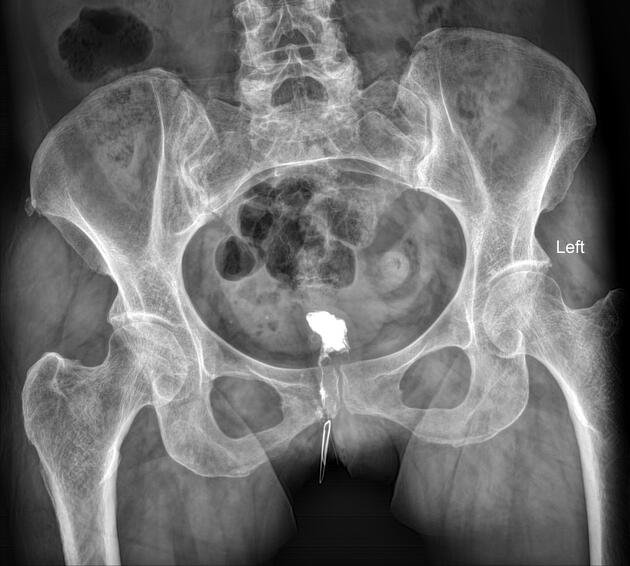

A fistulogram is a diagnostic imaging procedure used to evaluate the size, shape, and pathway of a fistula. A fistula is an abnormal connection between two body parts or passageways. These commonly occur between hollow organs such as the vagina, bladder, colon, or rectum. A fistulogram helps physicians accurately identify the structure and extent of the abnormal connection for proper diagnosis and treatment planning.

A fistulogram is performed by inserting a small needle or catheter into the dialysis fistula or graft after the area is cleaned and numbed with a local anesthetic. A special contrast dye is then injected into the blood vessel, which allows the doctor to clearly see the blood flow using X-ray imaging. These images help identify any narrowing, blockage, or other issues in the dialysis access so the doctor can determine the best treatment if needed.